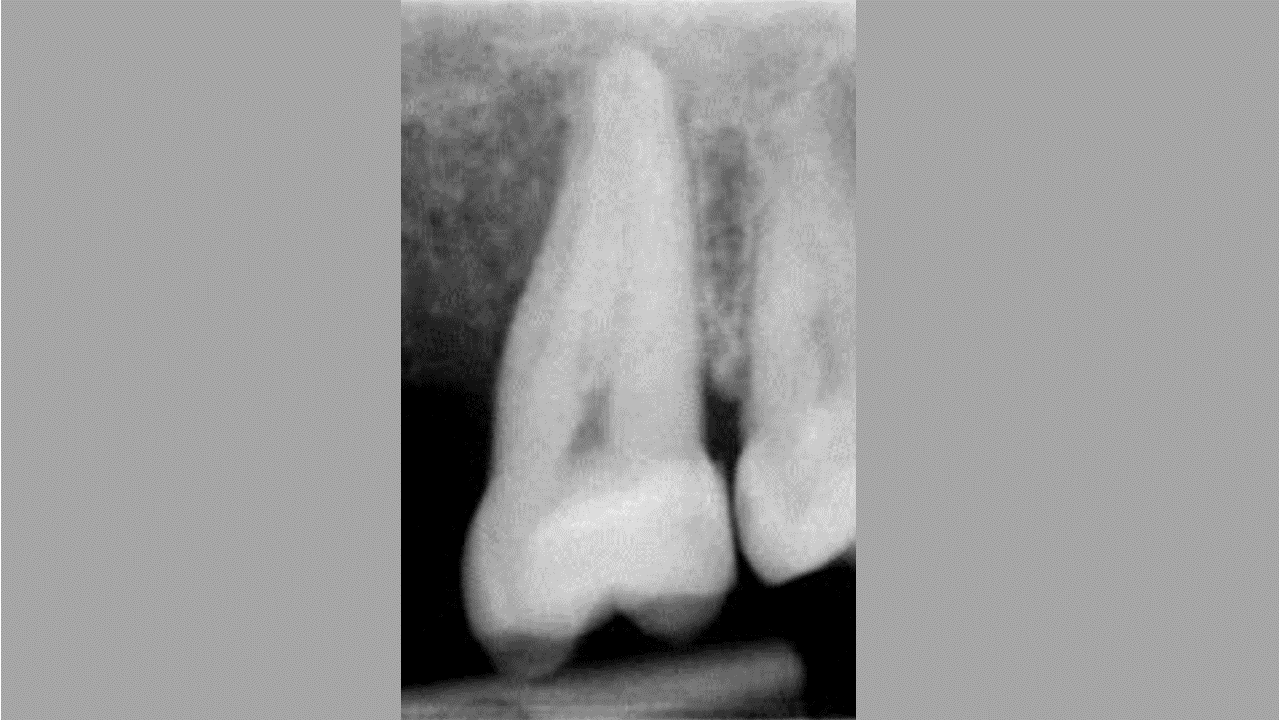

Treatment of vertical bone loss by using cerabone®, autologous bone and Jason® membrane - Prof. Rafael Ortega Lopes

The patient presented with severe pain in the lateral incisor and a deficient adhesive provisional. Bruxism resulted in canine loss and premature contact in the lateral incisor.